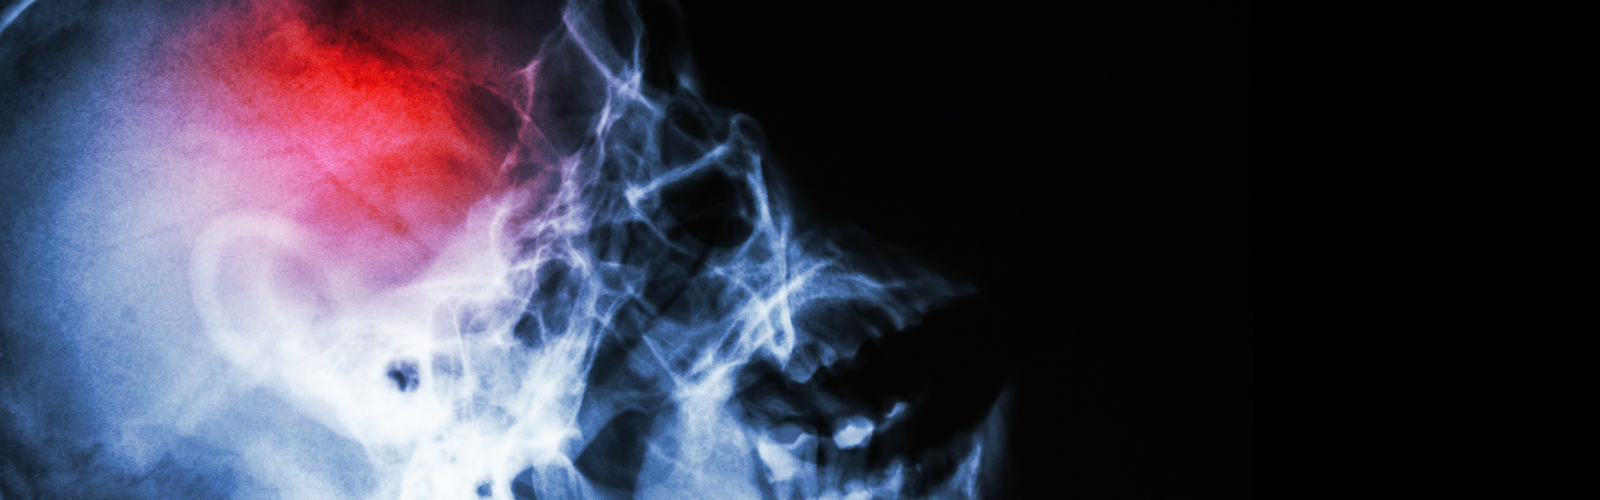

Neurocirugía

en uno de los más reconocidos programas de tumores cerebrales, base de cráneo y Neuro-Oncología -

- Estoy altamente entrenado para realizar abordajes de mínima invasión en cráneo y columna.